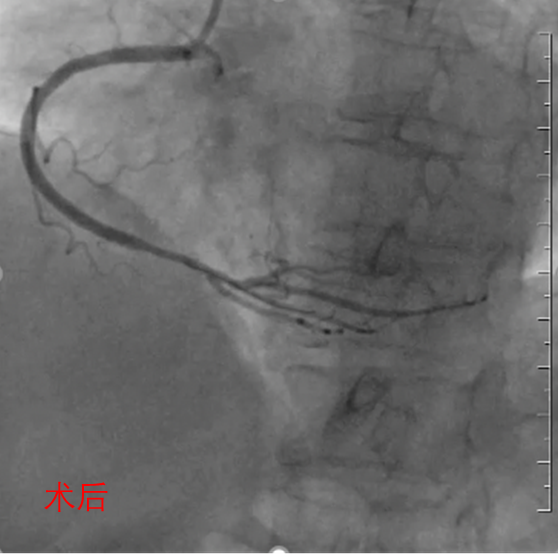

手术过程:

•本次治疗先处理RCA,择期处理LCX;

•先送2.5*15mm预扩球囊至RCA病变处预扩张,造影示狭窄明显减轻,未见明显夹层、造影剂外渗等;

•送1枚2.5*18mm BioFreedom®支架至病变处后定位释放(10atm3s),再送2.512mm NC球囊至支架内由远及近后扩张(14-16atm*3s) ;

•经多体位造影示支架扩张良好,TIMI血流3级。